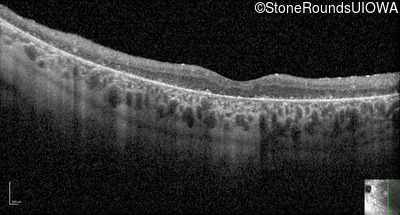

Optical Coherence Tomography - Left - 5/300

Exemplar / OCT Stack

OCT Stack